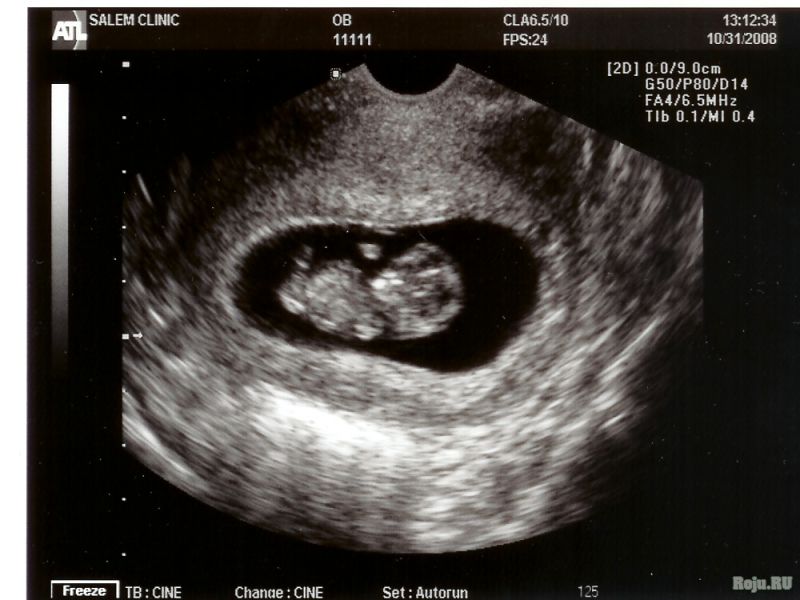

- трансвагинальный (дает более точную картину на ранних сроках, когда эмбрион еще небольшой);

- стандартный, или скриннинговый (проводится через переднюю брюшную стенку и дает черно-белое двухмерное изображение);

На ранней степени дифференцировки половые органы плодов обоих полов очень похожи, и их можно отличить друг от друга только с помощью аппаратуры с высокой степенью разрешения, например, 4D.